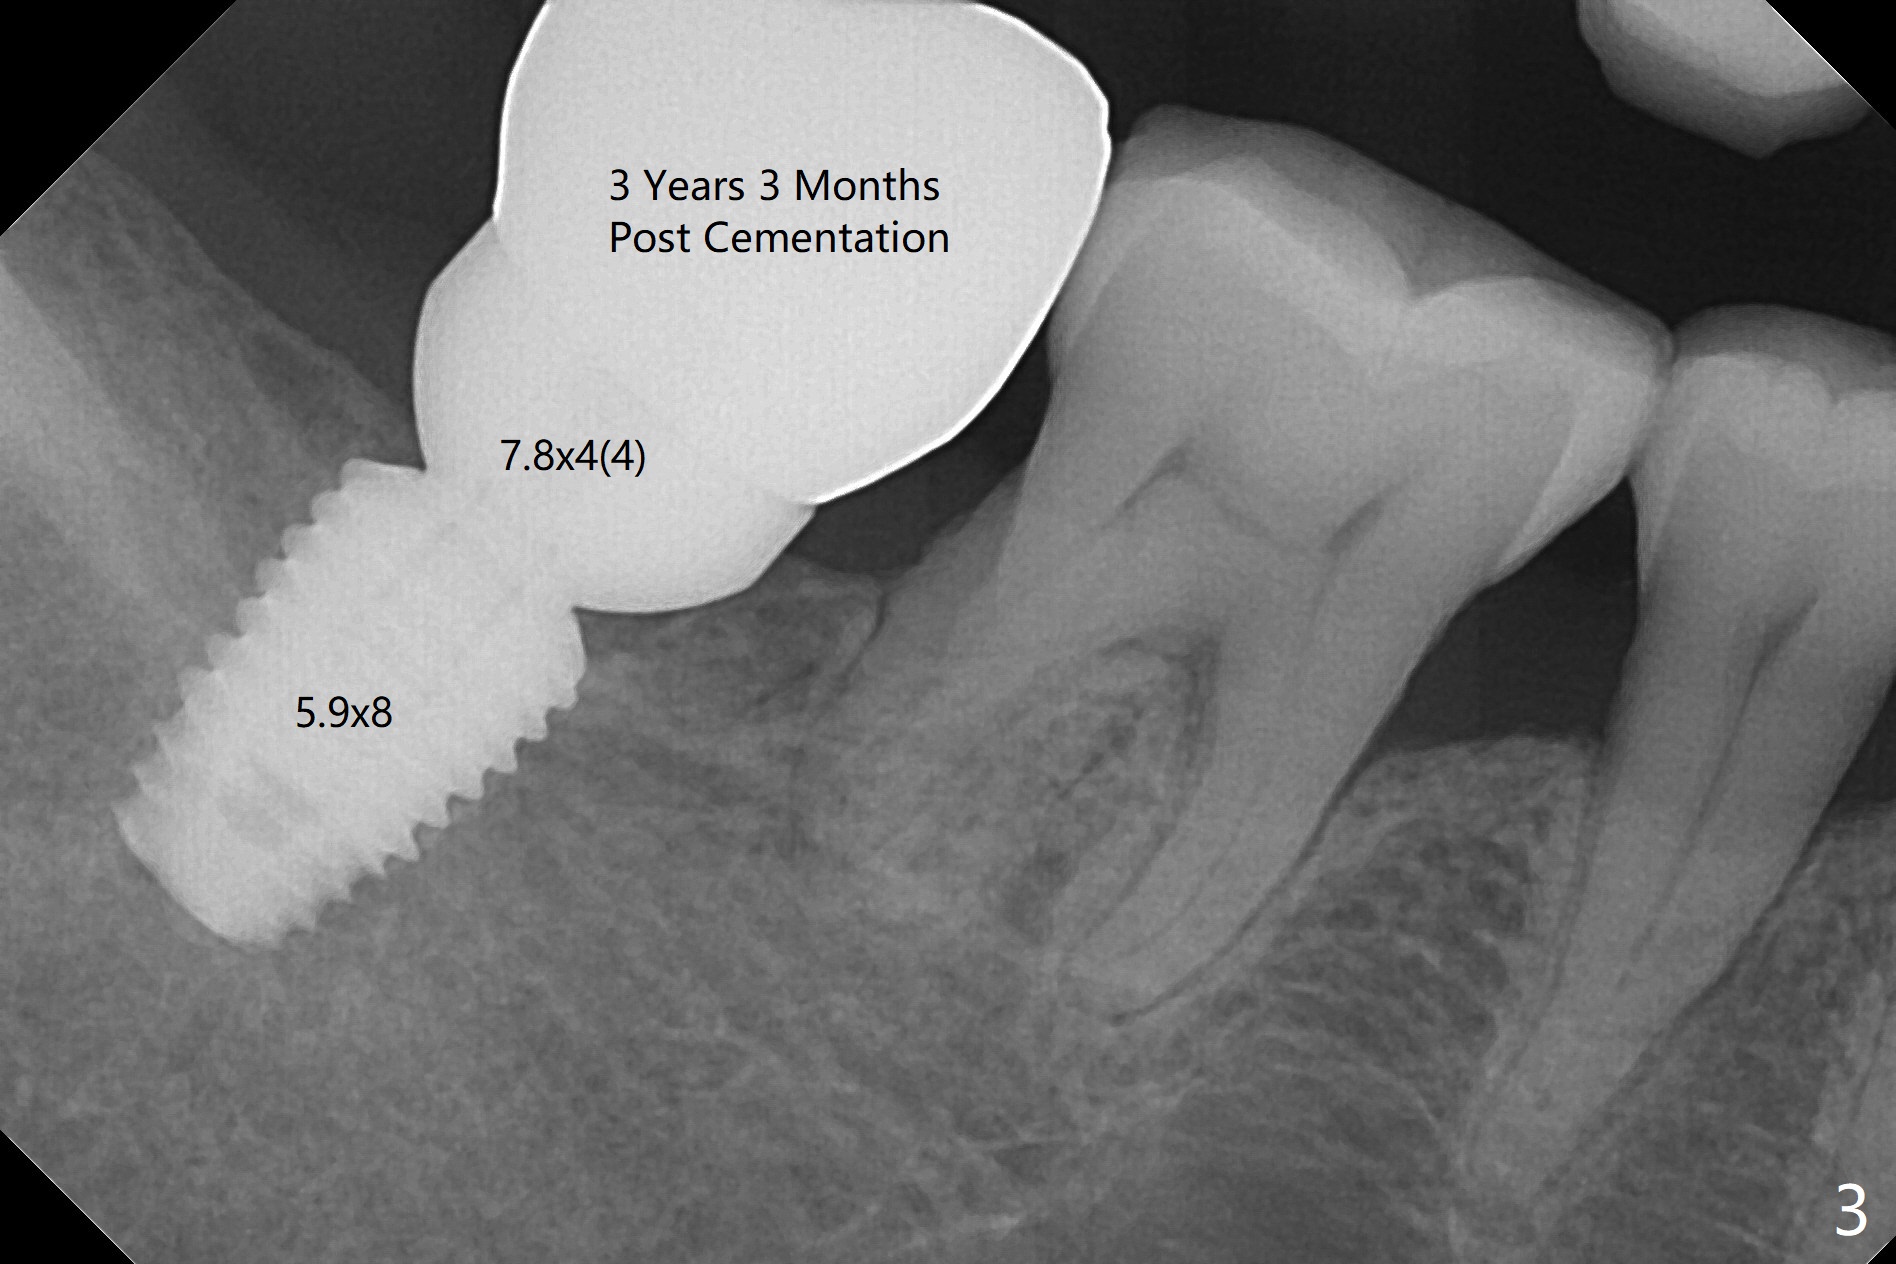

A 52-year-old woman returns for follow up 2-3 years post cementation (Fig.1-3). A smaller implant in the anterior maxilla appears to be associated with bone growth (Fig.1 * (#8)), as compared to a larger one (Fig.2 (#10)). There is apparently no bone loss at #31 (Fig.3).